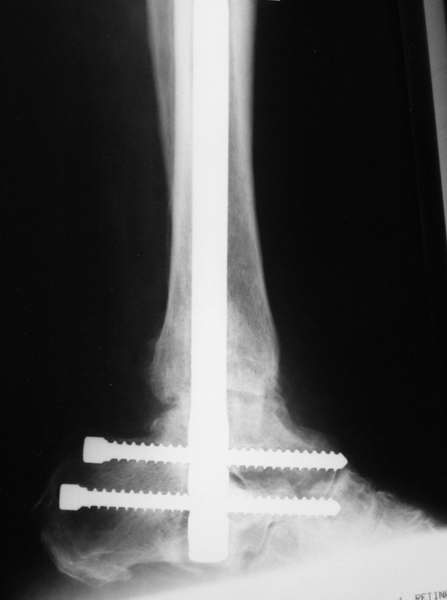

Можно: 65-летняя пациентка, оперирована по поводу несросшегося в гипсе перелома лодыжек с патологической вальгусной установкой стопы и выраженным нарушением опрной функции. Оперирована через 6 месяцев после травмы. Рентгенограммы через 4 месяца после операции.

Да. Изначально планируется и подтаранный артродез.